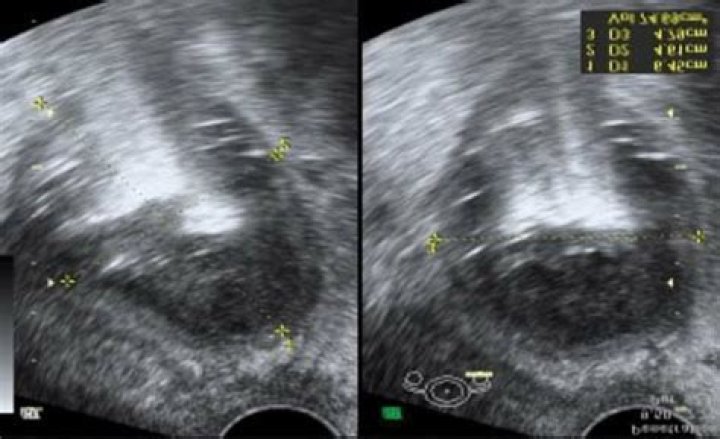

TOA appears as a complex solid or cystic mass on ultrasound. Abscesses may appear on one or both sides of the ovaries. Once a clinician ascertains the size and location of any abscesses, they can use this information to inform the next steps in treatment.

11 The classic findings of acute PID on transvaginal ultrasound are tubal wall thickness greater than 5 mm, incomplete septae within the tube, fluid in the cul-de-sac, and the cogwheel sign (a cogwheel appearance on the cross-section tubal view).

What does a tubo-ovarian abscess look like?

It is an inflammatory mass involving the fallopian tube, ovary and, occasionally, other adjacent pelvic organs. A TOA can also develop as a complication of a hysterectomy….Tubo-ovarian abscess.

Tubo-ovarian abscesses(TOA)